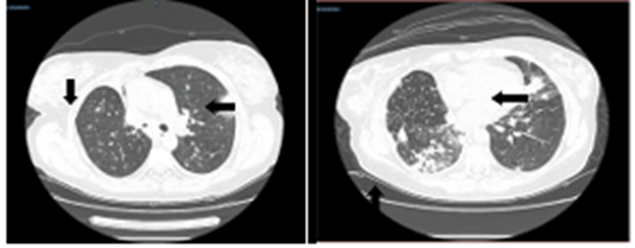

По данным мультиспиральной компьютерной томографии (МСКТ) органов грудной клетки (ОГК) при поступлении: во всех сегментах с обеих сторон определялись зоны уплотнения очагово-сливного характера на фоне утолщенного интерстиция. Состояние после атипичной резекции верхней доли справа. Проходимость трахеи, долевых и сегментарных бронхов сохранена. В плевральных полостях жидкость в следовом количестве. Было сделано заключение: КТ-картина двусторонней полисегментарной пневмонии. Двусторонний малый гидроторакс (рис. 1).

Рис. 1. МСКТ ОГК от 24.03.2024: во всех сегментах с обеих сторон зоны уплотнения очагово-сливного характера на фоне утолщенного интерстиция.

Источник: составлено авторами по результатам данного исследования